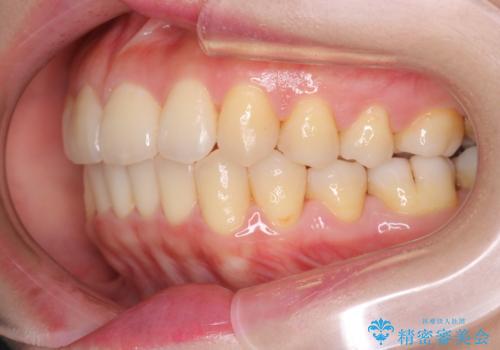

前歯が前後反対にかんでいる インビザラインによる目立たない矯正

- 前歯のかみ合わせを主訴に来院されました。

なるべく目立たずに矯正をしたいとのことで、インビザラインで矯正をすることとしました。

歯と歯の間をわずかに削り、ガタガタを改善しました。

目立たずに矯正を終えることができて、喜んでいただけました。